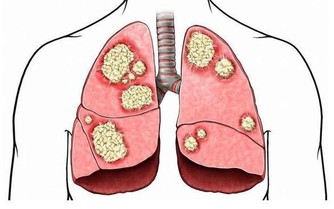

8,紫菜中的藻紅蛋白能與胰島素抗體發生免疫結合反應, 具有一定降血糖的功效,紫菜藻藍蛋白還能夠抑制腫瘤細胞的生長。

各類惡性腫瘤、乳腺小葉增生、腳氣病、水腫、白髮、脫髮、睪丸腫痛等患者常食用好處多。